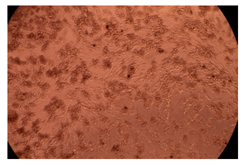

The results of the cytotoxicity assay, given in Figure 5, indicate that the tested PMs at all three established concentrations (10, 50, and 100 µg/mL) did not show cytotoxic effects on fibroblast cells at either 24 or 48 h after incubation. The percentages of cell viability were high, over 90%, in cells that were exposed to a concentration of 10 µg/mL for 24 h for all tested materials. Even at 48 h after incubation, the percentage of cell viability was as high as 90.4% in cells exposed to a concentration of 10 µg/mL for the Cop B sample. For both drug-loaded PMs, the cell viability decreased slightly at all tested concentrations. It also appears that the Dorzolamide-loaded PMs have slightly lower cell viability as compared to IMC-loaded PMs. Micrographs of the fibroblast cells after incubation times of 24 and 48 h are provided in Table 2.

Table 2.

Micrographs of fibroblast cells after 24 and 48 h incubation times, respectively.

As the cell viability values are all over 80%, the results indicate that the PMs, at the established concentrations, can be used successfully for in vivo biomedical applications.